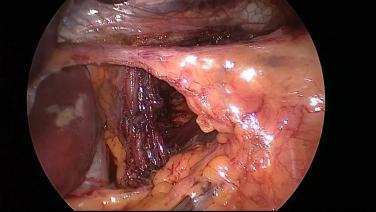

Demostración paso a paso de una reparación de hernia hiatal, con el Dr. Blair Jobe